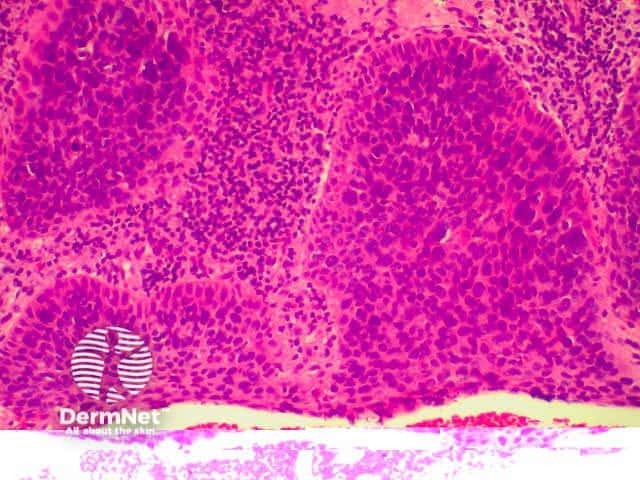

Invasive squamous cell carcinoma (SCC) is characterised by dermal invasion. Link to a clinical description of invasive squamous cell carcinoma.

SCC is characterised by proliferation of irregular nests of abnormal squamous cells arising from the epidermis and invading the dermis. Tumours are traditionally divided into well, moderately or poorly differentiated tumours by a subjective assessment of how significantly the tumour cells differ from normal keratinocytes. In general, the greater the degree of keratinization, the better differentiated the tumour is thought to be. Except in the case of very poorly differentiated tumours, this does not have a great bearing on prognosis. More important is the depth and irregularity of invasion, particularly the presence of perineural infiltration, which is associated with a much higher rate of recurrence if not widely excised. The site of the lesion is also important; tumours of the lips and ears have a considerably higher rate of metastasis to lymph nodes.

There are several descriptive variants of SCC including spindle cell SCC and acantholytic (or adenoid or pseudoglandular SCC). These mainly are of note due to the difficulty of diagnosing the tumour as SCC, but they may also imply a slightly worse prognosis. A further rare variant is verrucous carcinoma, a lesion in which the histology has a deceptively benign appearance in that there is very little cytological abnormality. Diagnosis in these cases may be delayed and the diagnosis may not be made until several biopsies have been performed. These tumours recur locally, but do not generally metastasise.

From the above comments it can be seen that the histological features of SCCs can vary, but in general are:

Pathology of SCC Pathology of SCC Pathology of SCC Pathology of SCC